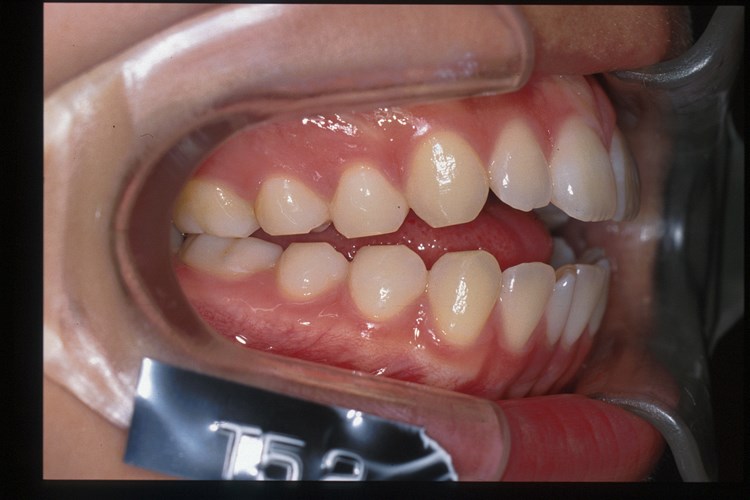

After右側貌

Before

Afterリボン歯科・矯正歯科グループは、インビザライン矯正の高精度、スピーディ、快適な治療の為にiTero(口腔内スキャナ)をグループで18台導入しております。